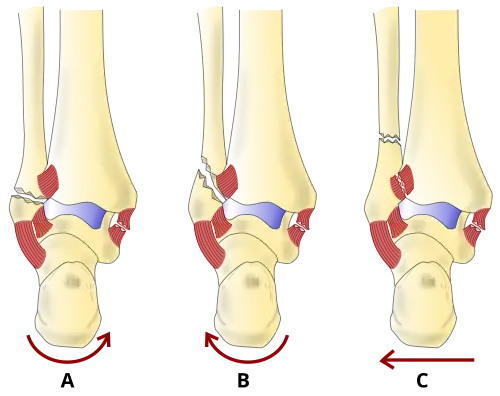

The Danis–Weber classification (often known just as the Weber classification) is a method of describing ankle fractures. It has three categories:[1]

- Type A

Fracture of the fibula distal to the syndesmosis (the connection between the distal ends of the tibia and fibula). Typical features:

- Type B

Fracture of the fibula at the level of the syndesmosis. Typical features:

- Type C

Fracture of the fibula proximal to the syndesmosis. Typical features: